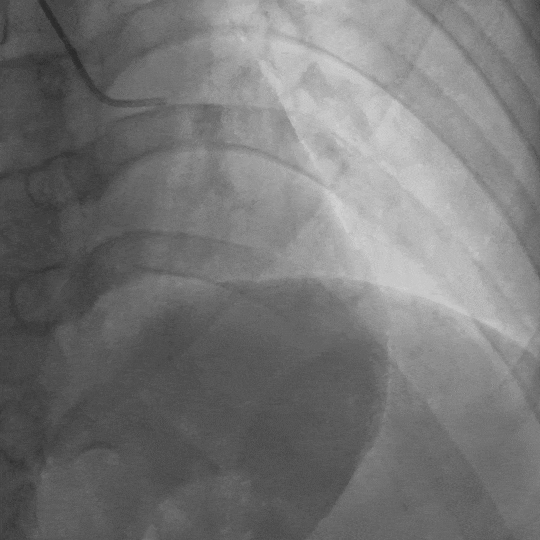

影像素材 | 患者冠状动脉造影 1:前降支中段长段心肌桥,收缩期管腔重度狭窄

影像素材 | 患者冠状动脉造影 2:前降支中段长段心肌桥,收缩期管腔重度狭窄